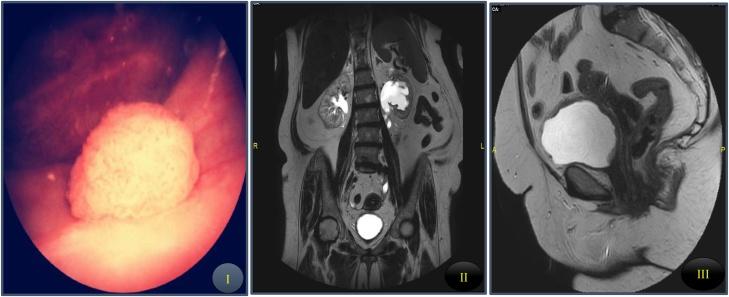

PRESENTATION OF CASE

A-64 years old female presented with sever irritative lower urinary tract symptoms (LUTS) post vesical BCG installation for carcinoma in situ. Patient's symptoms were relieved after Botox bladder injection after anticholinergics failure. One year later, she came back with hematuria. Cystoscopy showed nodular bladder lesion. Hypertension episodes were noticed during cystoscopic resection. Pathological examination showed presence of muscle invasive transitional cell carcinoma (TCC) with neuroendocrine differentiation. Patient underwent radical cystectomy and pathology was associated with incidentally discovered primary ovarian paraganglioma.

病例介绍

一名64岁女性在膀胱内灌注卡介苗治疗原位癌后出现严重的刺激性下尿路症状(LUTS)。在抗胆碱能药物治疗失败后,肉毒素膀胱注射使患者症状得到缓解。一年后,她因血尿复诊。膀胱镜检查显示膀胱有结节性病变。在膀胱镜切除过程中发现有高血压发作。病理检查显示存在伴有神经内分泌分化的肌层浸润性移行细胞癌(TCC)。患者接受了根治性膀胱切除术,病理检查偶然发现原发性卵巢副神经节瘤。